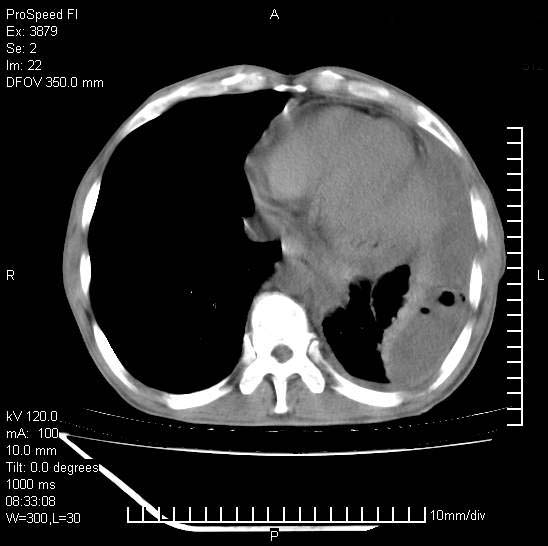

以下是引用37度在2008-6-6 11:20:00的发言:[br]1.包裹性积液,多考虑结核性;[br]2.穿刺术后改变。